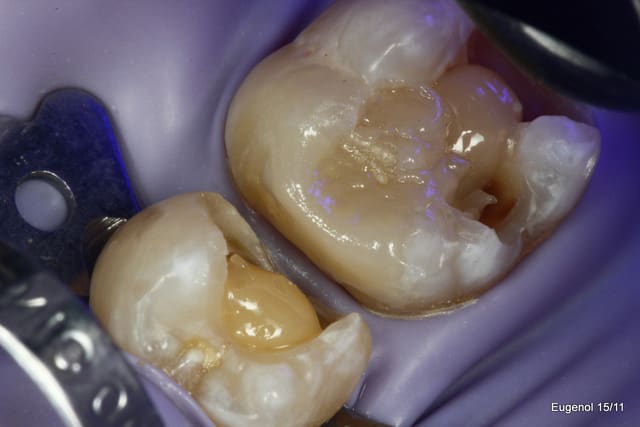

un truc que je fais souvent, quand je monte deux compo volumineux en contact, je monte le plus gros et difficile sans matrice et comme ça j'ai accès a la marge, et je peux donner une jolie forme galbée proximale

puis je monte le suivant avec une seule matrice...

plus facile je trouve d'avoir le point de contact

Je propose cette approche dans les cas particulier où l'on a deux box volumineux face à face. Il est difficile dans ses cas d'obtenir un point de contact efficace.

Je le fais quand je peux facilement avoir accès à la spatule à toute la face proximale